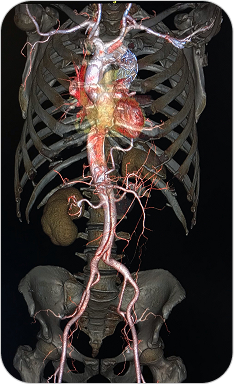

ANGIOTAC

La Angiotomografía es un estudio que utiliza tomografía computada multislice y contraste intravenoso para obtener imágenes detalladas de los vasos sanguíneos. En este caso, permite evaluar de forma precisa la aorta torácica y abdominal, incluyendo sus ramas principales.

La angiotomografía es un estudio especializado para visualizar la aorta y sus ramas principales, detectando enfermedades vasculares con gran precisión.

¿PARA QUE SE UTILIZA?

- Detección y seguimiento de aneurismas de aorta.

Diagnóstico de disección aórtica (emergencia vascular). - Evaluación de estenosis, malformaciones o traumatismos vasculares.

- Estudio previo a cirugías cardiovasculares o colocación de endoprótesis (stent).

- Valoración de arterias renales, mesentéricas y troncos viscerales.

¿POR QUÉ ES UN ESTUDIO DESTACADO?

- Alta resolución y detalle anatómico de la aorta y sus ramas.

Estudio rápido, no invasivo y bien tolerado. - Ideal para urgencias vasculares y planificación quirúrgica.

- Permite reconstrucciones en 3D para mejor visualización por parte del cirujano vascular.

Reconstrucción 3D en Tomografía

Es una técnica avanzada que permite convertir las imágenes obtenidas por tomografía computada en modelos tridimensionales. Estas reconstrucciones permiten visualizar estructuras anatómicas de forma realista, facilitando diagnósticos más precisos y una mejor planificación quirúrgica o terapéutica.

Las reconstrucciones tridimensionales a partir de tomografía computada permiten visualizar la anatomía de forma realista y precisa, facilitando diagnósticos y cirugías complejas.

¿PARA QUE SE UTILIZA?

- Evaluación detallada de fracturas complejas, articulaciones y columna vertebral.

- Estudio anatómico previo a cirugías (traumatológicas, maxilofaciales, cardiovasculares).

- Visualización de vasos sanguíneos, tumores o malformaciones desde distintos ángulos.

- Planificación prequirúrgica más segura y personalizada.

- Educación médica y explicación visual a pacientes.

¿POR QUÉ ES UN ESTUDIO DESTACADO?

- Imágenes más claras y comprensibles para médicos y pacientes.

Facilita una mayor precisión diagnóstica. - Permite una visión global y tridimensional de la anatomía.

- Complemento ideal para especialidades como traumatología, neurocirugía, cirugía maxilofacial y oncología.

ANGIOTAC

La Angiotomografía es un estudio que utiliza tomografía computada multislice y contraste intravenoso para obtener imágenes detalladas de los vasos sanguíneos. En este caso, permite evaluar de forma precisa la aorta torácica y abdominal, incluyendo sus ramas principales.

La angiotomografía es un estudio especializado para visualizar la aorta y sus ramas principales, detectando enfermedades vasculares con gran precisión.

¿PARA QUE SE UTILIZA?

- Detección y seguimiento de aneurismas de aorta.

Diagnóstico de disección aórtica (emergencia vascular). - Evaluación de estenosis, malformaciones o traumatismos vasculares.

- Estudio previo a cirugías cardiovasculares o colocación de endoprótesis (stent).

- Valoración de arterias renales, mesentéricas y troncos viscerales.

¿POR QUÉ ES UN ESTUDIO DESTACADO?

- Alta resolución y detalle anatómico de la aorta y sus ramas.

Estudio rápido, no invasivo y bien tolerado. - Ideal para urgencias vasculares y planificación quirúrgica.

- Permite reconstrucciones en 3D para mejor visualización por parte del cirujano vascular.

Reconstrucción 3D en Tomografía

Es una técnica avanzada que permite convertir las imágenes obtenidas por tomografía computada en modelos tridimensionales. Estas reconstrucciones permiten visualizar estructuras anatómicas de forma realista, facilitando diagnósticos más precisos y una mejor planificación quirúrgica o terapéutica.

Las reconstrucciones tridimensionales a partir de tomografía computada permiten visualizar la anatomía de forma realista y precisa, facilitando diagnósticos y cirugías complejas.